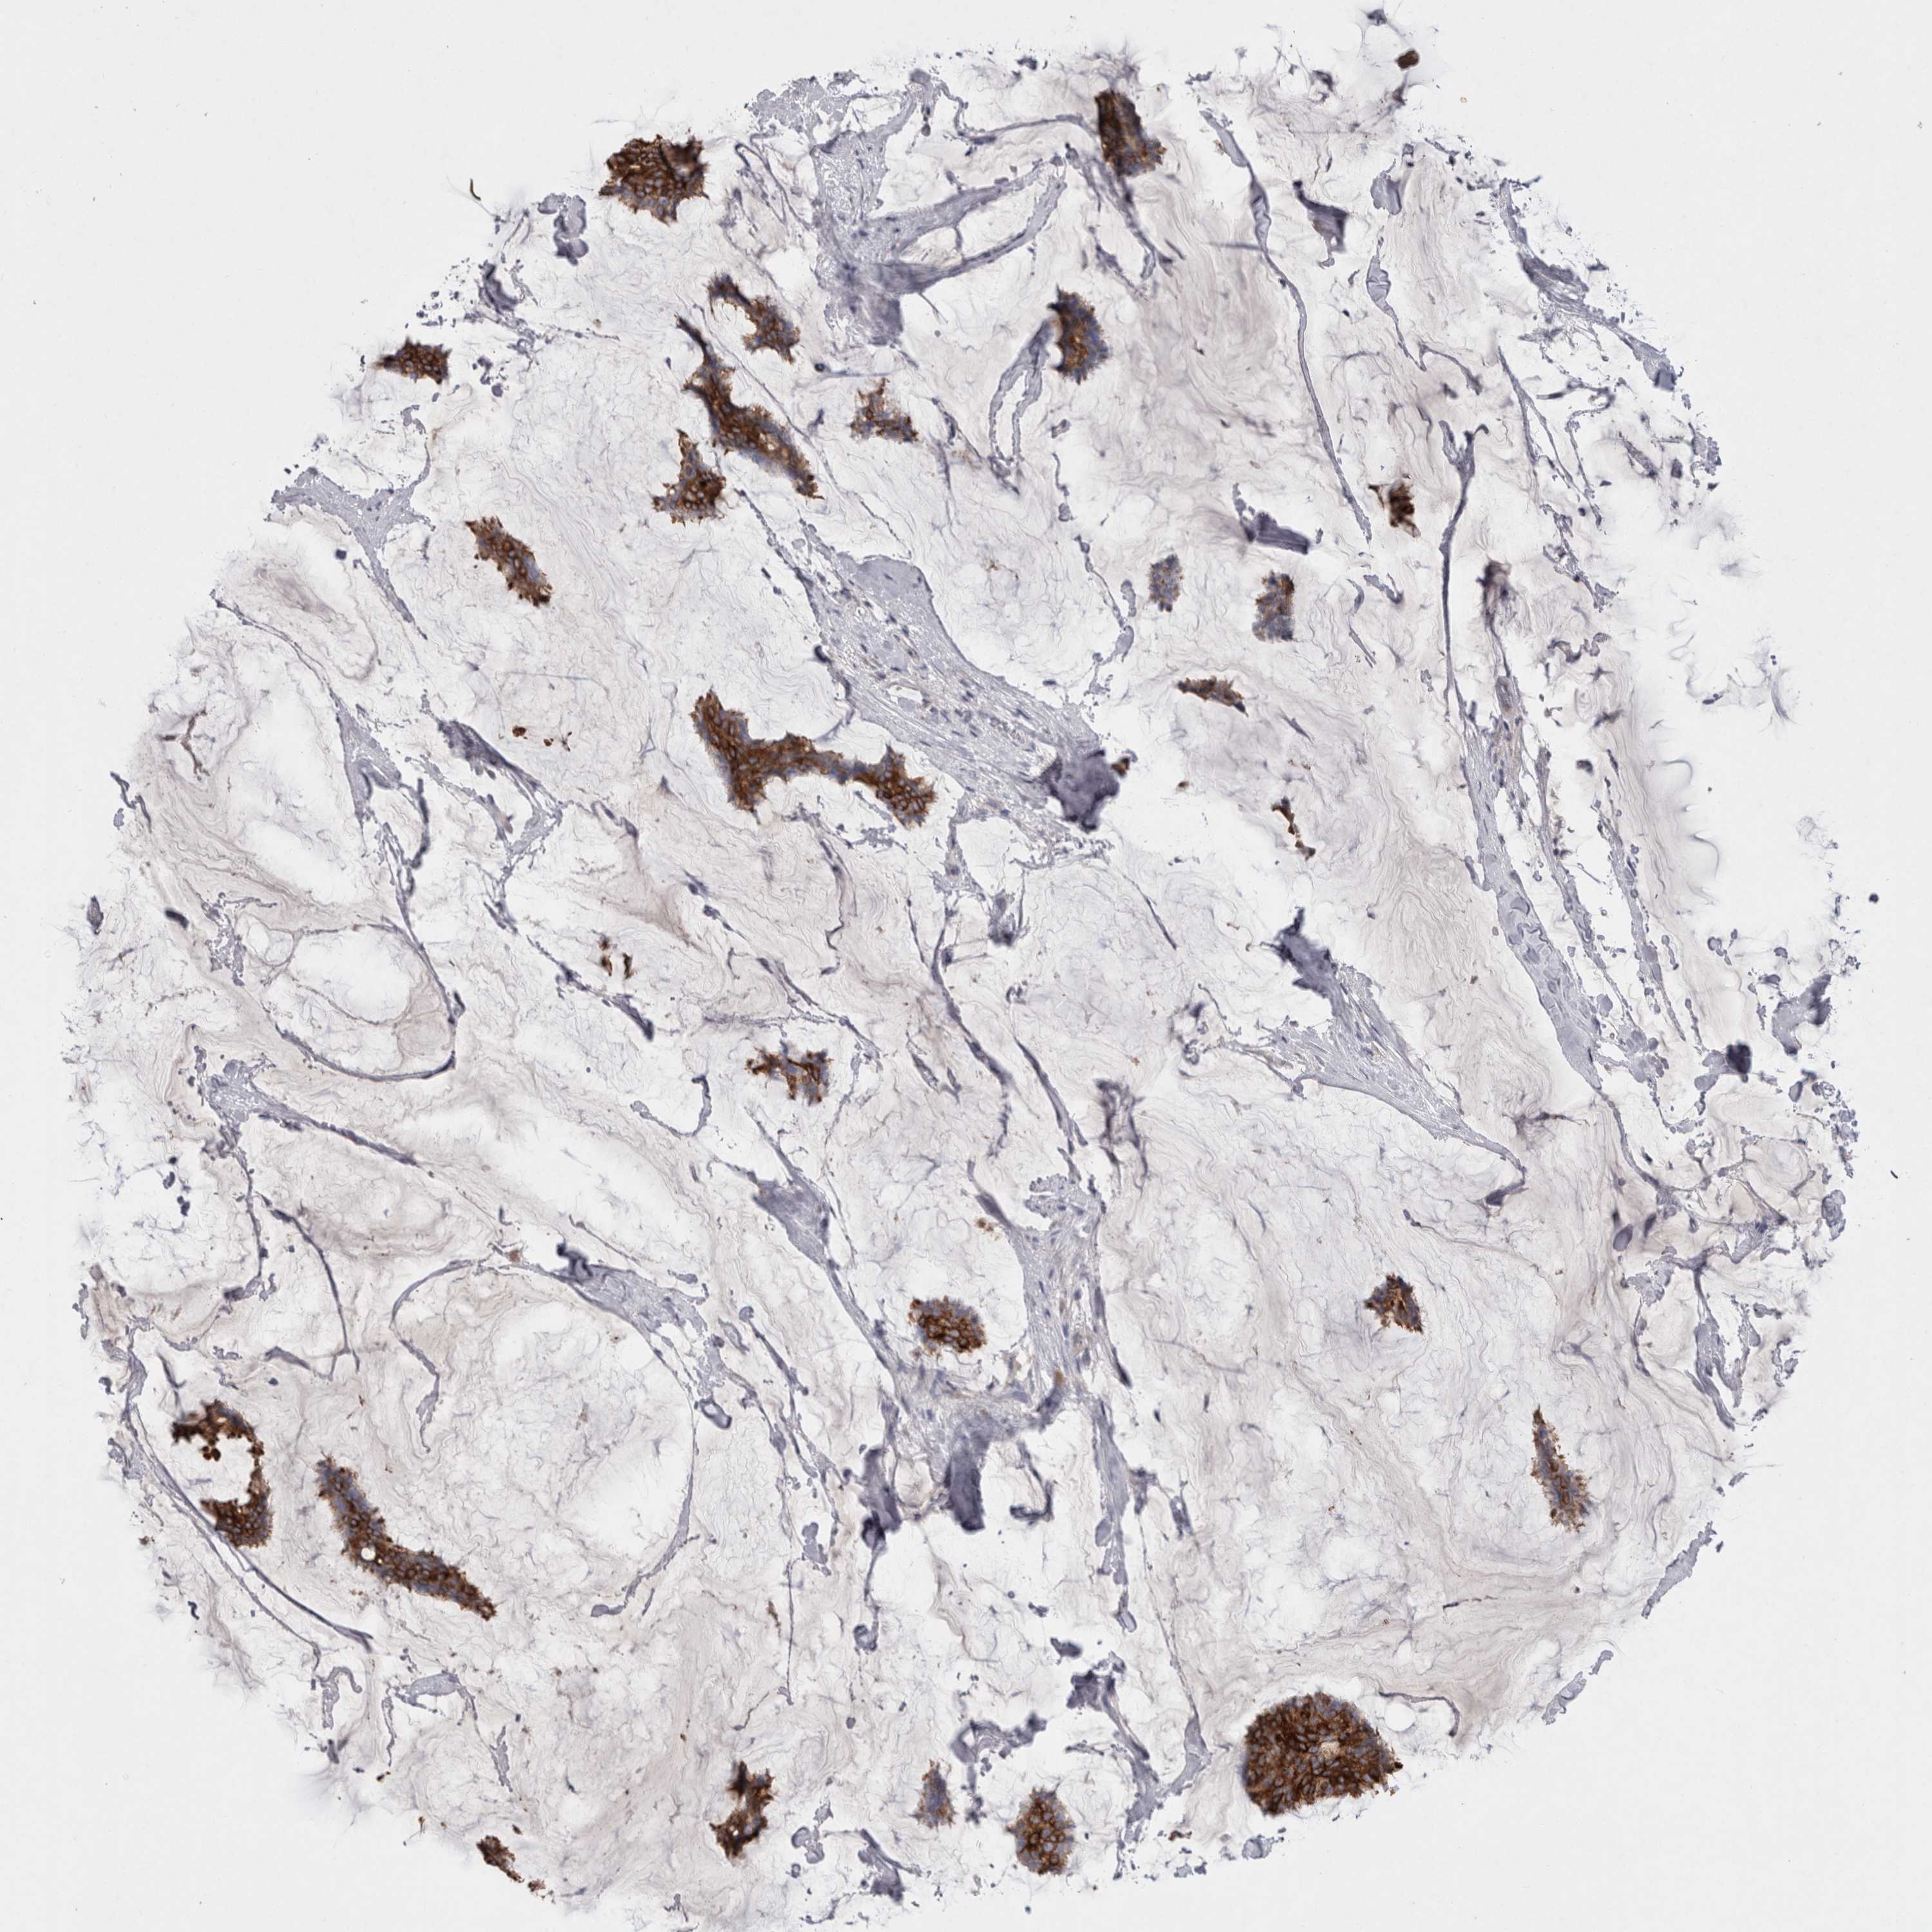

CANCER BREAST CANCER Show tissue menu

BRCA TCGA BRCA VALIDATION PROTEIN EXPRESSION